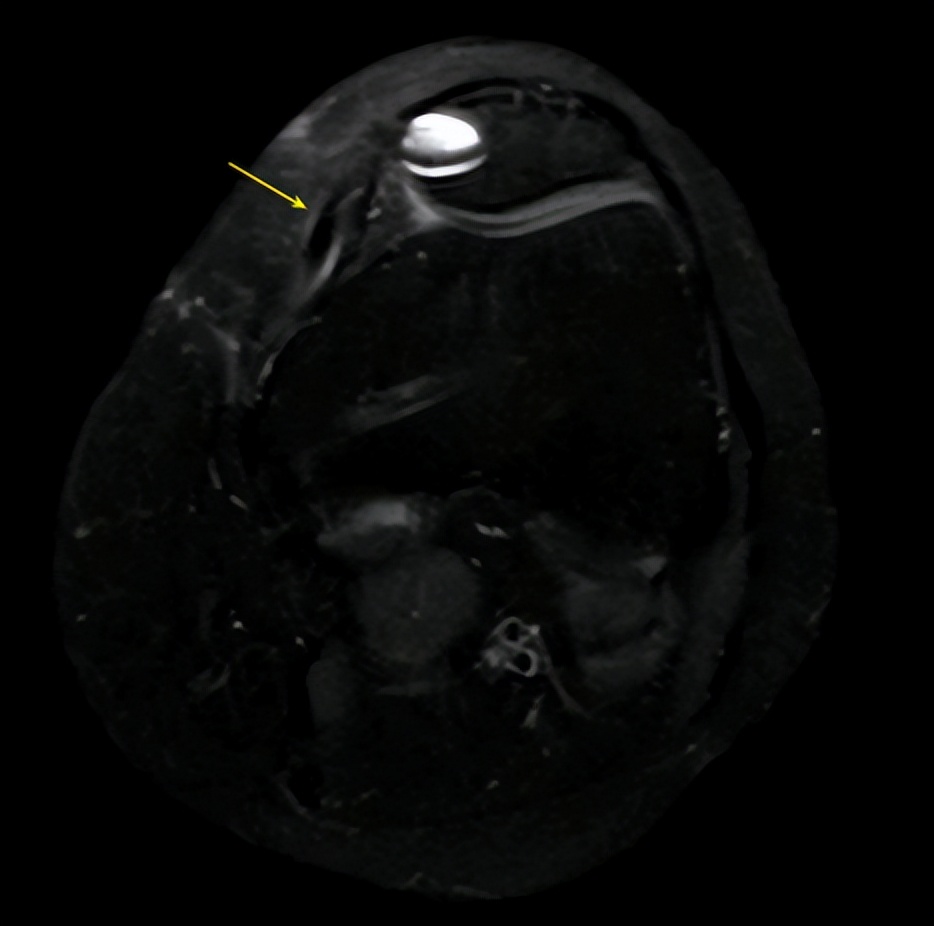

△术前可见髌股韧带断裂(左图),术后可见重建的韧带(右图)

对于杨女士的病情,何河北医生制定了个性化微创治疗方案,使用杨女士自身肌腱为她重建了髌骨内测支持韧带,简称“MPFL重建”。

在手术中,何河北医生先在杨女士的同侧小腿,取出一段肌腱(半腱肌),然后在她的膝盖骨两端分别开了2cm切口,里面制作了一个凹槽,再将肌腱放入膝盖骨凹槽中,用两枚带线锚钉固定住肌腱,最后通过透视定位,将其固定于股骨收肌结节上方。

何河北医生介绍:“MPFL重建的原理,就是使用自体肌腱一端使用锚钉固定于髌骨,另外一端牵拉使得外脱位的髌骨有内向的牵引力,恢复髌股轨迹,而这一端肌腱使用挤压螺钉固定于收肌结节。”